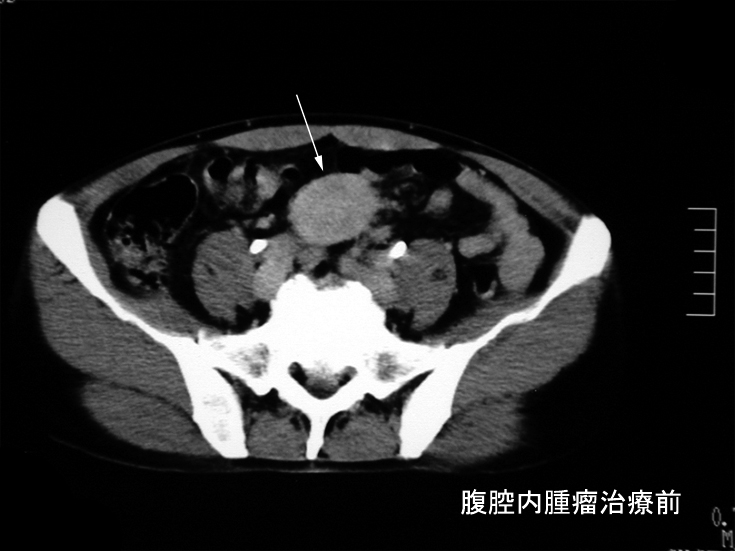

本性例のERCP画像では主膵管とその分枝にあきらかな狭窄所見や壁の不整を認めない。 膵には頭部(CT画像なし),尾部に腫瘤が形成されている。

腹腔内には静脈を巻き込むように血管周囲に腫瘤の形成がある。(クリックで大きな画像が見られます)